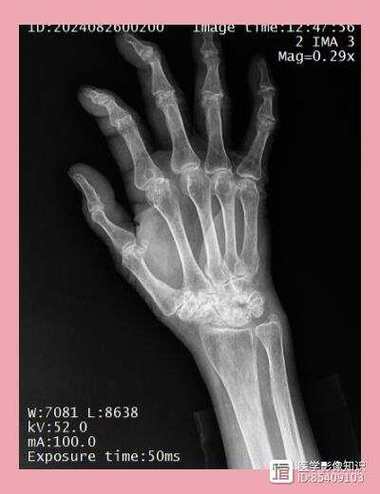

X光片主要观察的是骨骼和关节的结构变化,在类风湿关节炎中,这些变化是由于长期的滑膜炎症侵蚀了软骨和骨骼导致的。

- 仅见软组织肿胀: 可以看到关节周围的组织因为积液和炎症而显得肿胀、密度增高,但这不是特异性的,其他关节炎也可能有此表现。

- 轻微的骨质疏松: 受累关节周围的骨骼可能出现脱钙、密度降低的情况,这是因为炎症导致局部血流增加,骨骼代谢加快,骨量丢失,这也是比较早期的非特异性表现。

- 关节间隙狭窄: 这是最关键的X光表现之一,正常软骨在X光下是看不见的,所以关节间隙其实是软骨的厚度,当类风湿关节炎的炎症侵蚀掉软骨后,X光片上就能看到关节之间的空隙变窄了。

- 骨侵蚀: 这是另一个最具诊断价值的特征,炎症的增厚滑膜(血管翳)会像“癌细胞”一样,从关节边缘开始侵蚀骨骼,在X光片上形成边缘清晰的、小洞样的骨质缺损,常见于手指、手腕的掌骨头和指骨的基底部。

- 关节畸形: 当软骨和骨骼被严重破坏,关节周围的韧带和肌腱也因炎症而松弛或断裂时,关节就会失去正常的对位关系,导致畸形,例如手指的“天鹅颈”样畸形、“钮扣花”样畸形,手腕的尺偏畸形等。